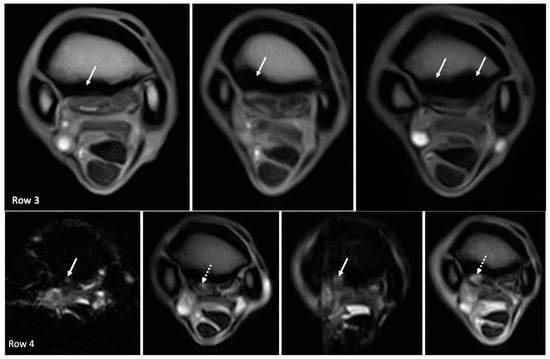

| Dorsal margin irregularity of the PSL | 12/18 (75%) | - | - | 12/12 (100%) | - |

| Hyperintense signal on T1W GRE and T2*W GRE within the dorsal collagenous part of the PSL | 11/18 (61%) | 0/11 | 6/11 (55%) | 4/11 (36%) | 1/11 (9%) |

| Hyperintense STIR signal within the dorsal collagenous part of the PSL | 5/18 (28%) | 4/5 (80%) | - | 1/5 (20%) | - |

| Dorsal margin irregularity of the PSL | Grade 0: 5 limbs Grade 1: 7 limbs Grade 2: 6 limbs Grade 3: 0 limbs | Grade 0: 5 limbs Grade 1: 7 limbs Grade 2: 6 limbs Grade 3: 0 limbs |

| Hyperintense signal on T1W GRE and T2*W GRE within the dorsal collagenous part of the PSL | Grade 0: 7 limbs Grade 1: 5 limbs Grade 2: 5 limbs Grade 3: 1 limb | Grade 0: 7 limbs Grade 1: 10 limbs Grade 2: 1 limbs Grade 3: 0 limbs |

| Hyperintense STIR signal within the dorsal collagenous part of the PSL | Grade 0: 13 limbs Grade 1: 1 limb Grade 2: 4 limbs Grade 3: 0 limb | Grade 0: 17 limbs Grade 1: 0 limbs Grade 2: 1 limbs Grade 3: 0 limbs |